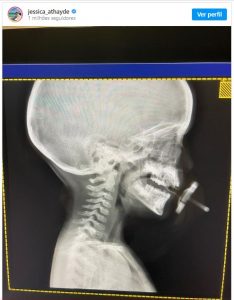

Jessica Athayde voltou a ser criticada após ter partilhado nas redes sociais, um raio-X do filho, Oliver.

Oliver, de três anos fez um raio-X e a mãe, a atriz da SIC, partilhou nas redes sociais. Para não variar, acabou por ser criticada. Na legenda podemos ler, “Sou só eu ou o raio-X do Oli parece uma obra de arte?”

“És só tu, Jessica Athayde. Não sei o que lhe aconteceu, mas irradiar o cérebro de uma criança tão pequena e anda mais com uma exposição de uma área tão grande, parece-me mau e preocupante. Só em Portugal é que ainda se acha graça ao raio-X (quanto mais melhor) e se pede ao médico, quase por favor, para se fazer mais um”, atirou.

No entanto a atriz acabou por reagir, “Não estás boa da cabeça. Alguma vez eu faria um raio-X ao meu filho só porque sim”.